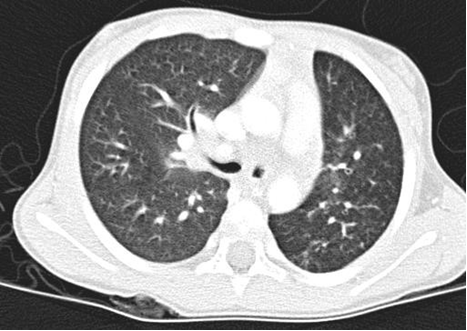

Where available a High-resolution computed tomography (HRCT) scanning is the standard test for diagnosis especially in the absence of characteristic chest radiograph findings of dilated airway, with thickened airway walls. Key features on CT scan: Enlarged internal bronchial diameter with bronchi that appear larger than the accompanying artery. Other findings include the failure of the larger airways to taper while progressing to the lung periphery, air fluid levels in the dilated airways, and the identification of airways in the extreme lung periphery. Other testing may be indicated to diagnose underlying conditions.